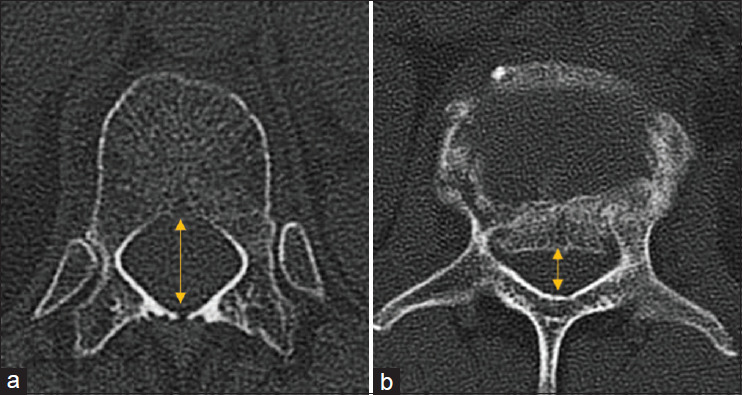

Materials and methods: A retrospective analysis was conducted on 101 patients who underwent short posterior fixation with transpedicular Schanz screws between 2012 and 2022 for single-level (T12 or L1) TLBFs. Clinical outcomes (Oswestry Disability Index [ODI] and Visual Analog Scale [VAS]) and radiological parameters (sagittal alignment and spinal canal dimensions) were assessed with a minimum 2-year follow-up.

Results: A total of 101 TLBFs patients with an average age of 48.1 years (range: 26-65) were included in this study. Intraoperative reduction of the Sagittal Kyphosis (SK) achieved an average of 12.31° ± 8.1°°, with a mean sagittal index (SI) correction of 15.23° ± 4.24°. At a minimum 2-year follow-up, the total amount of kyphosis reduction was maintained, with no significant difference between immediate postoperative and early follow-up measurements. Load-sharing score >8, body mass index >26, preoperative radiological parameters (SI, SK, and anterior body height [ABH] ratio), and postoperative ABH ratio were identified as significant predictors of correction loss >10°. At the final follow-up, all patients had minimal disability, with an average ODI of 7.9%. VAS scores also showed significant improvement, indicating substantial clinical effectiveness of the Schanz screw system in managing these complex spinal injuries.